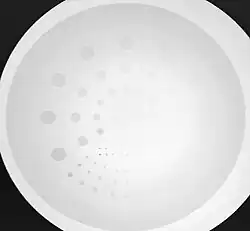

- Contrast-detail evaluation combines physical indices of image quality with observer detection ability. Contrast-detail phantoms contain test objects of different sizes and subject contrast mounted on a plastic plate that is radiographed under specific exposure conditions - see Figure 6.20. Contrast-detail plots are derived on the basis of the borderline visibility of test objects in the image. A disadvantage of this approach however is the introduction of bias as a result of the observer's prior knowledge of the size, shape and location of the low-contrast objects. The link between this type of evaluation and clinical imaging performance is therefore difficult to establish.